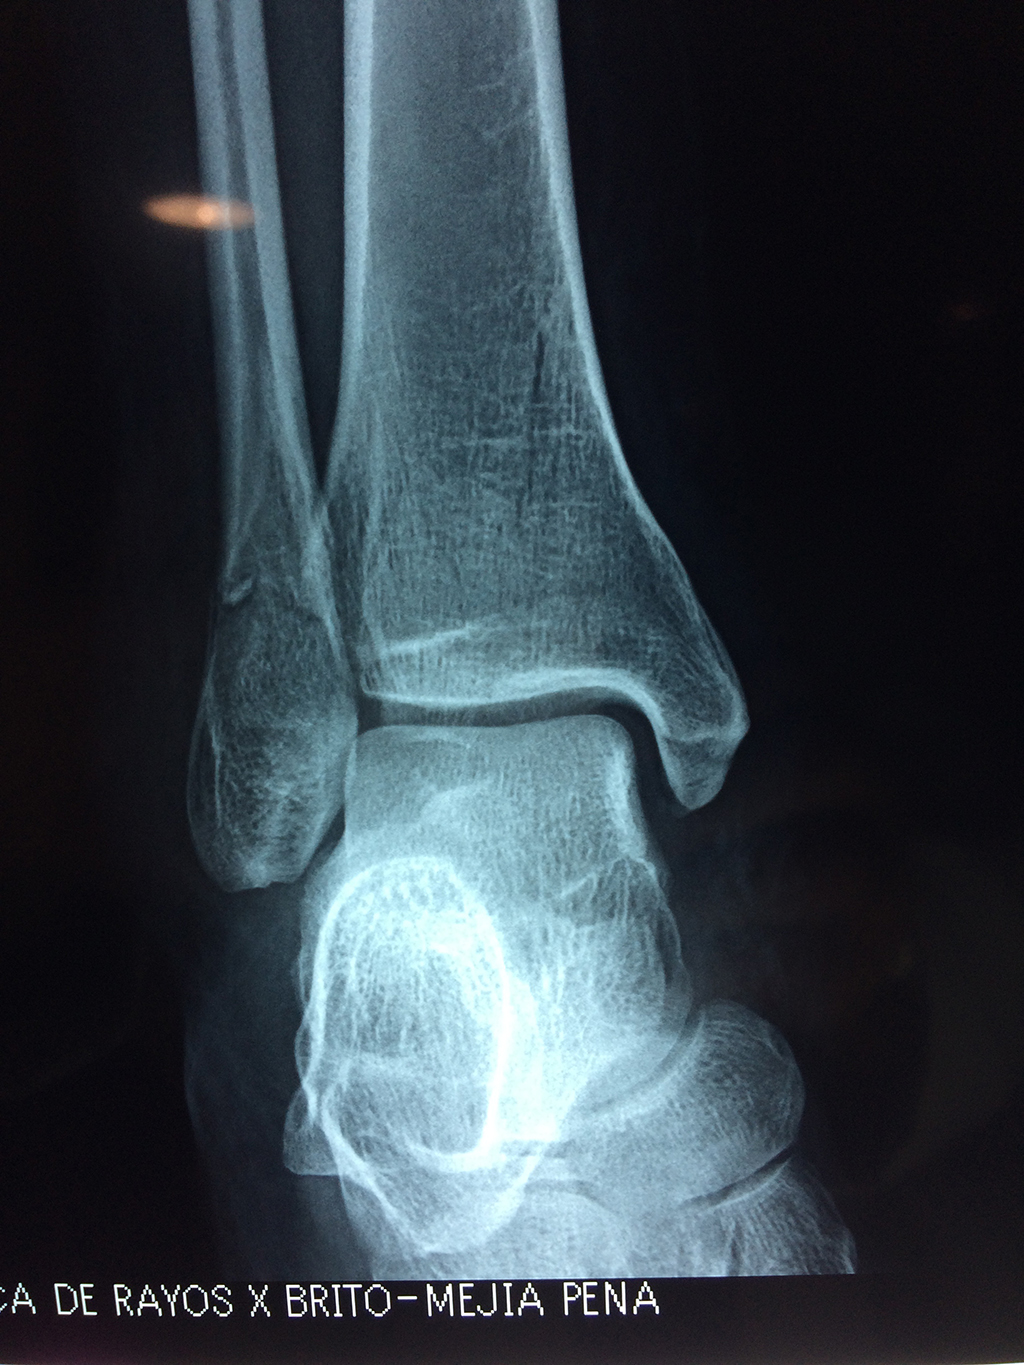

Una fractura de tobillo es la rotura de uno o más de los huesos del tobillo. Estas fracturas pueden ser:

- Los extremos de los huesos están desalineados entre sí (desplazados).

- La fractura se extiende hasta la articulación del tobillo (fractura intra-articular).

- Los tendones o ligamentos (tejidos que sujetan los músculos y los huesos entre sí) están rotos.

Cuando se necesita cirugía, es probable que esta implique el uso de clavijas de metal, tornillos o placas para sostener los huesos en su lugar mientras la fractura se consolida. Los elementos de soporte pueden ser temporales o permanentes.